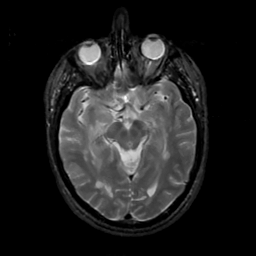

MR Study #6, March 17, 1991 -- Slice #21

[Home][Help][Clinical][Tour 1][Tour 2] Slice 21